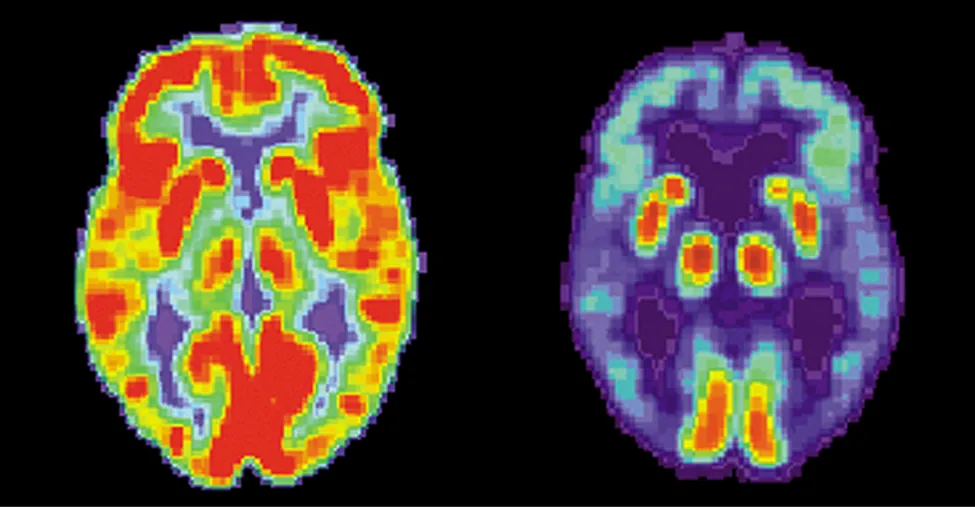

Pokazano dwa obrazy mózgu. Ten po lewej stronie ma wiele czerwonych i pomarańczowych obszarów oraz trochę niebieskich obszarów. Ten po prawej stronie jest głównie niebieski z bardzo małymi obszarami w kolorze czerwonym i żółtym.

Ilustracja 10.26 Te obrazy mózgu zostały wytworzone przy użyciu radiofarmaceutyku. Kolory wskazują względną aktywność metaboliczną lub biochemiczną (kolor czerwony oznacza wysoką aktywność, a niebieski – aktywność niską). Rysunek po lewej stronie pokazuje normalny mózg człowieka, a rysunek po prawej – mózg osoby z rozpoznaną chorobą Alzheimera. Obraz zdrowego mózgu wykazuje dużo większą aktywność metaboliczną (większy udział obszarów czerwonych i pomarańczowych). Źródło: National Institutes of Health, USA